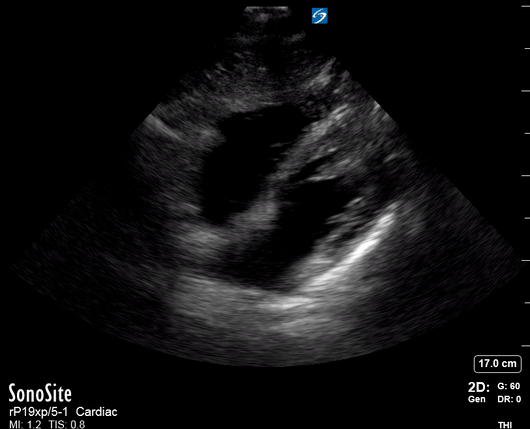

The A4C view provides an accurate chamber size comparison. However, achieving a proper A4C view (avoiding foreshortening or ballooning, and visualising the four chambers with a vertically oriented interventricular septum) can be a challenging exercise of image acquisition. Additionally, the PSAX view at the level of the papillary muscles shows both LV and RV side by side and is useful to assess function and size. When RV pressure is high, the septum will be pushed and flattened towards the LV, resulting in the characteristic “D-shaped” LV or “D sign”.

PITFALLS

When comparing size, beware of correct image acquisition, as oblique planes lead to misinterpreting the RV:LV ratio. For apical views be sure to slide the probe sufficiently laterally on the chest wall so that it lies over the true apex. Also, be sure to obtain a real horizontal plane, avoiding foreshortening (ballooning). For the PLAX view it is useful to fan through the heart’s long axis, making sure that LV visualization is maximized relative to the RV. Furthermore, an understanding of probe placement and marker orientation conventions is fundamental. If inadvertently scanning in reverse orientation, the normally larger LV could be mistaken for an abnormally enlarged RV.